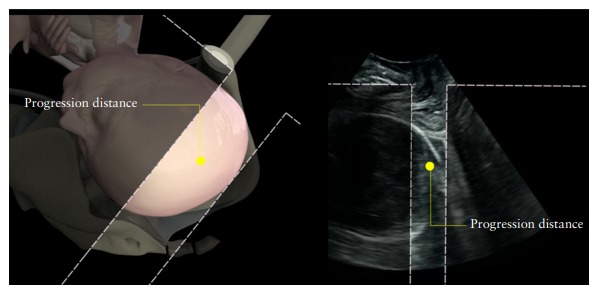

Após avaliação da localização de ambos os rins, características do parênquima, deve ser feita a avaliação da dilatação (pelviectasia) da pelve renal. A partir do início do segundo trimestre, a pelve renal torna-se detectável e os rins geralmente perdem sua aparência hiperecogênica anterior. A pelve renal sempre aparece como uma área sonolucente na medial dos rins ( Figura 1b ). A pelviectasia ou hidronefrose é avaliada nos cortes dos planos transversos abdominais fetais, por meio da medida do diâmetro ântero-posterior (DAP) da pelve renal, onde possível o dorso fetal fica perpendicular à sonda ( Figura 2a ). A dilatação da pelve renal pode diferir por semana gestacional, hidratação materna ou distensão da bexiga ( 5 – 7)